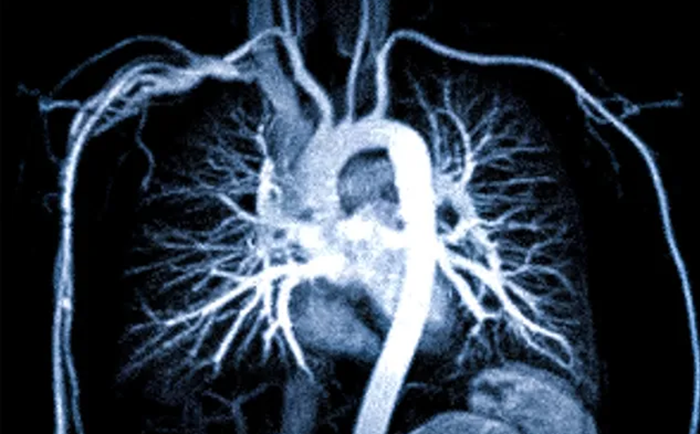

Аорта представляет собой самый мощный сосуд, отходящий от левого желудочка сердца. Часть аорты, расположенная в грудной полости, дает ответвления, которые питают верхнюю половину туловища, в том числе головной мозг. Легочные артерии являются продолжением легочного ствола, выходящего из правого желудочка сердца. Они несут венозную кровь в легкие, чтобы насытить ее кислородом для дальнейшего жизнеобеспечения организма.

Компьютерная томография дает снимки, по которым можно оценить состояние стенок сосудов, их форму, дефекты развития и пороки. Возможность построения трехмерного изображения дает методу дополнительную чувствительность и наглядность. Это делает компьютерную томографию методом выбора в диагностике в сложных клинических случаях.

Что лучше – МРТ или КТ грудной аорты и легочной артерии

В диагностике заболеваний грудной клетки предпочтительнее использовать компьютерную томографию. Это связано с принципом получения изображения. При проведении компьютерного исследования рентгеновский луч хорошо улавливает разницу между твердыми структурами, жидкостью и воздухом. Сосуды наполнены жидкостью, а легкие воздухом, поэтому изображение получается наиболее четким.